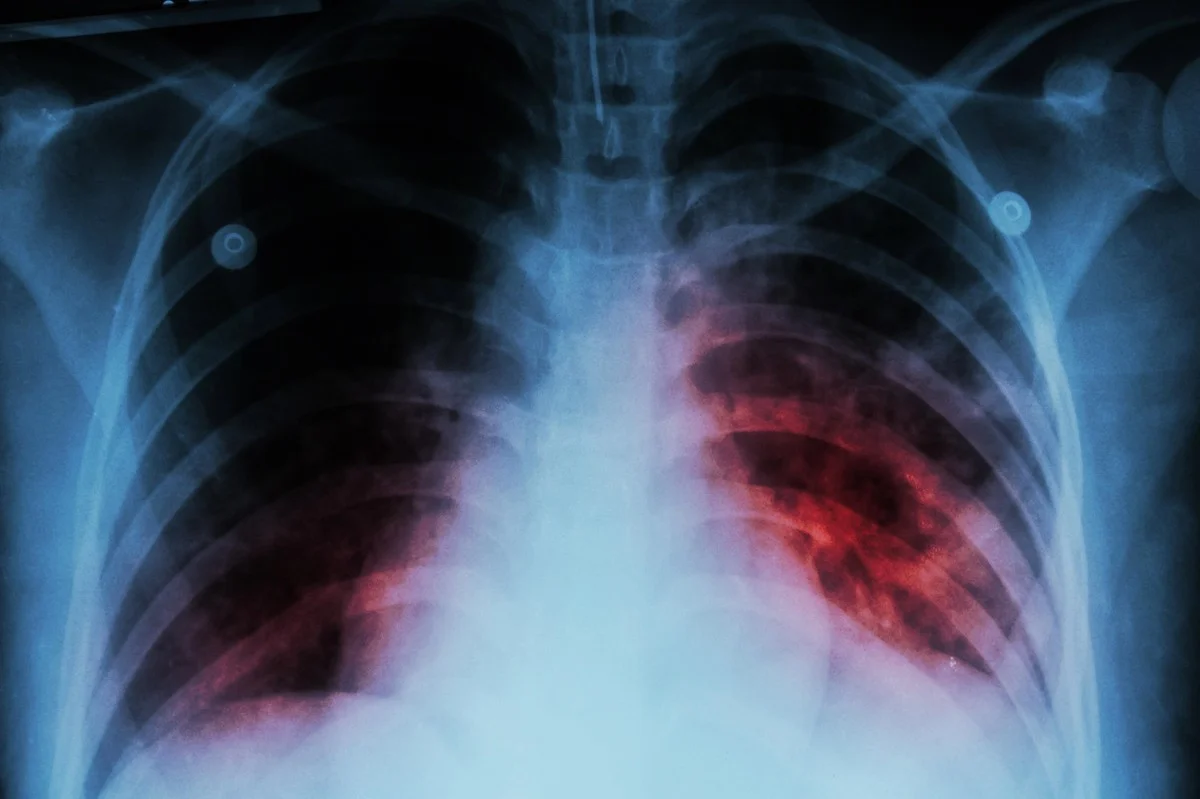

NEW YORK, Oct 30: In a recent report published by the World Health Organization (WHO) on Tuesday, tuberculosis (TB) has surpassed COVID-19 to become the leading cause of infectious disease-related deaths in 2023. The report underscores the ongoing challenges faced in the global fight to eradicate this disease.

According to the WHO, approximately 8.2 million people were newly diagnosed with TB last year, marking the highest figure recorded since the organization began global monitoring of the disease in 1995. This represents an increase from the 7.5 million cases reported in 2022.

While deaths related to TB decreased to 1.25 million in 2023 from 1.32 million in 2022, the total number of people falling ill with the disease rose slightly to an estimated 10.8 million. The WHO noted that global milestones and targets for reducing the disease burden are currently off-track, emphasizing the need for considerable progress to meet targets set for 2027.